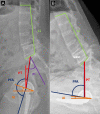

Acetabular component orientation and position are important factors in the short- and long-term outcomes of total hip arthroplasty. Different definitions of inclination and anteversion are used in the orthopaedic literature and surgeons should be aware of these differences and understand their relationships. There is no universal safe zone. Preoperative planning should be used to determine the optimum position and orientation of the cup and assess spinopelvic characteristics to adjust cup orientation accordingly. A peripheral reaming technique leads to a more accurate restoration of the centre of rotation with less variability compared with a standard reaming technique. Several intraoperative landmarks can be used to control the version of the cup, the most commonly used and studied is the transverse acetabular ligament. The use of an inclinometer reduces the variability associated with the use of freehand or mechanical alignment guides.